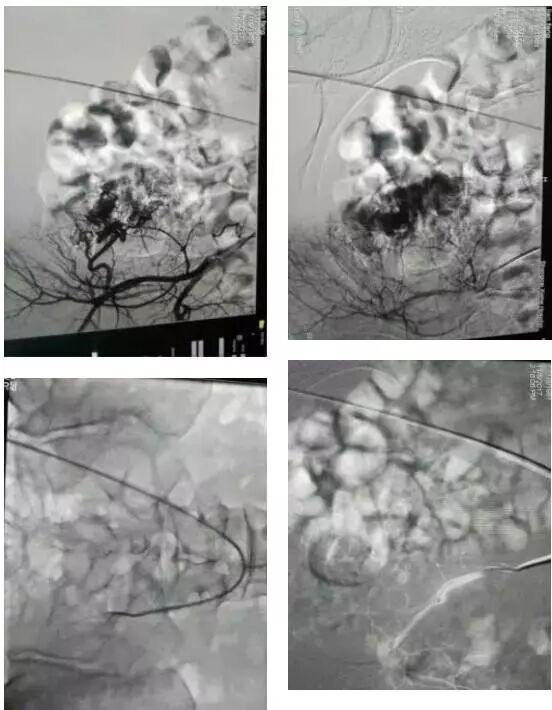

患者在局麻下成功施行微创介入治疗,即在局麻下用Selding技术先行右侧股动脉穿刺插管,用5F导管行双侧髂动脉造影术并DSA,术中观察双侧子宫动脉显示情况,再引入微导管超选择性进入双侧子宫动脉,经微导管缓慢注入栓塞微粒从而达到栓塞子宫末梢动脉的目的,术中患者无诉任何不适。于介入术后第3天进行了超声引导下清宫术,术中仅出血约50ml。术后患者恢复良好,疗效明显,一周后痊愈出院。

介入术中......

微创介入性治疗子宫切口瘢痕妊娠,作为保守治疗的微创技术,已在治疗妇产科疾病如产后出血、子宫肌瘤、子宫腺肌症、宫颈妊娠中等广泛应用,被认为是目前唯一可以取代子宫切除治疗大出血的技术。以往子宫切口瘢痕处妊娠大出血病例多行全子宫切除术。目前多提倡采用保守性治疗。该患者经妇科及超声、磁共振(MRI)检查诊断为剖宫产瘢痕部位妊娠,采用双侧子宫动脉栓塞术的方法,PVA颗粒栓塞剂一方面可迅速阻断血流,加速滋养叶细胞活性丧失,减少阴道大出血的发生,避免切除子宫导致失去生育能力;另一方面PVA颗粒12~24天即可为机体吸收使血管再通,从而最大限度地避免对正常子宫血供的影响。据我院介入专家介绍,子宫动脉栓塞术治疗剖宫产后瘢痕部位妊娠快速、安全、效果较好,妇科手术失血量明显减少,并可保留子宫,均可在术后1周内出院,HCG在两个月内恢复正常,与传统氨甲喋呤(MTX)保守治疗相比,可以明显缩短住院时间,且无发生大出血的危险,对病情危重的出血患者不失为值得选用的应急止血手段,介入治疗后,在B超监视下行清宫术,不但术中出血减少,还降低了手术的难度和风险,以防盲目刮宫造成子宫穿孔或甚至于切除子宫。

4.什么是选择性子宫动脉栓塞术?具体是怎么起到治疗作用的?当我们通过临床检查结合超声或磁共振(MRI)确诊瘢痕妊娠以后,选择血管介入治疗,在放射技术引导下,经皮股动脉穿刺插管,将导管超选择性分别插入双侧子宫动脉,然后注入可吸收的栓塞剂阻断病灶的主要供血动脉,减慢动脉血流并形成血栓,使病灶缺血而逐渐萎缩,从而达到止血、杀胚的治疗目的。目前可吸收栓塞剂主要选择PVA栓塞微粒球,一般两周左右即被溶解吸收,血管就可再通。所以选择性子宫动脉栓塞术是除子宫切除外治疗子宫切口瘢痕妊娠(CSP)的最佳治疗方法。